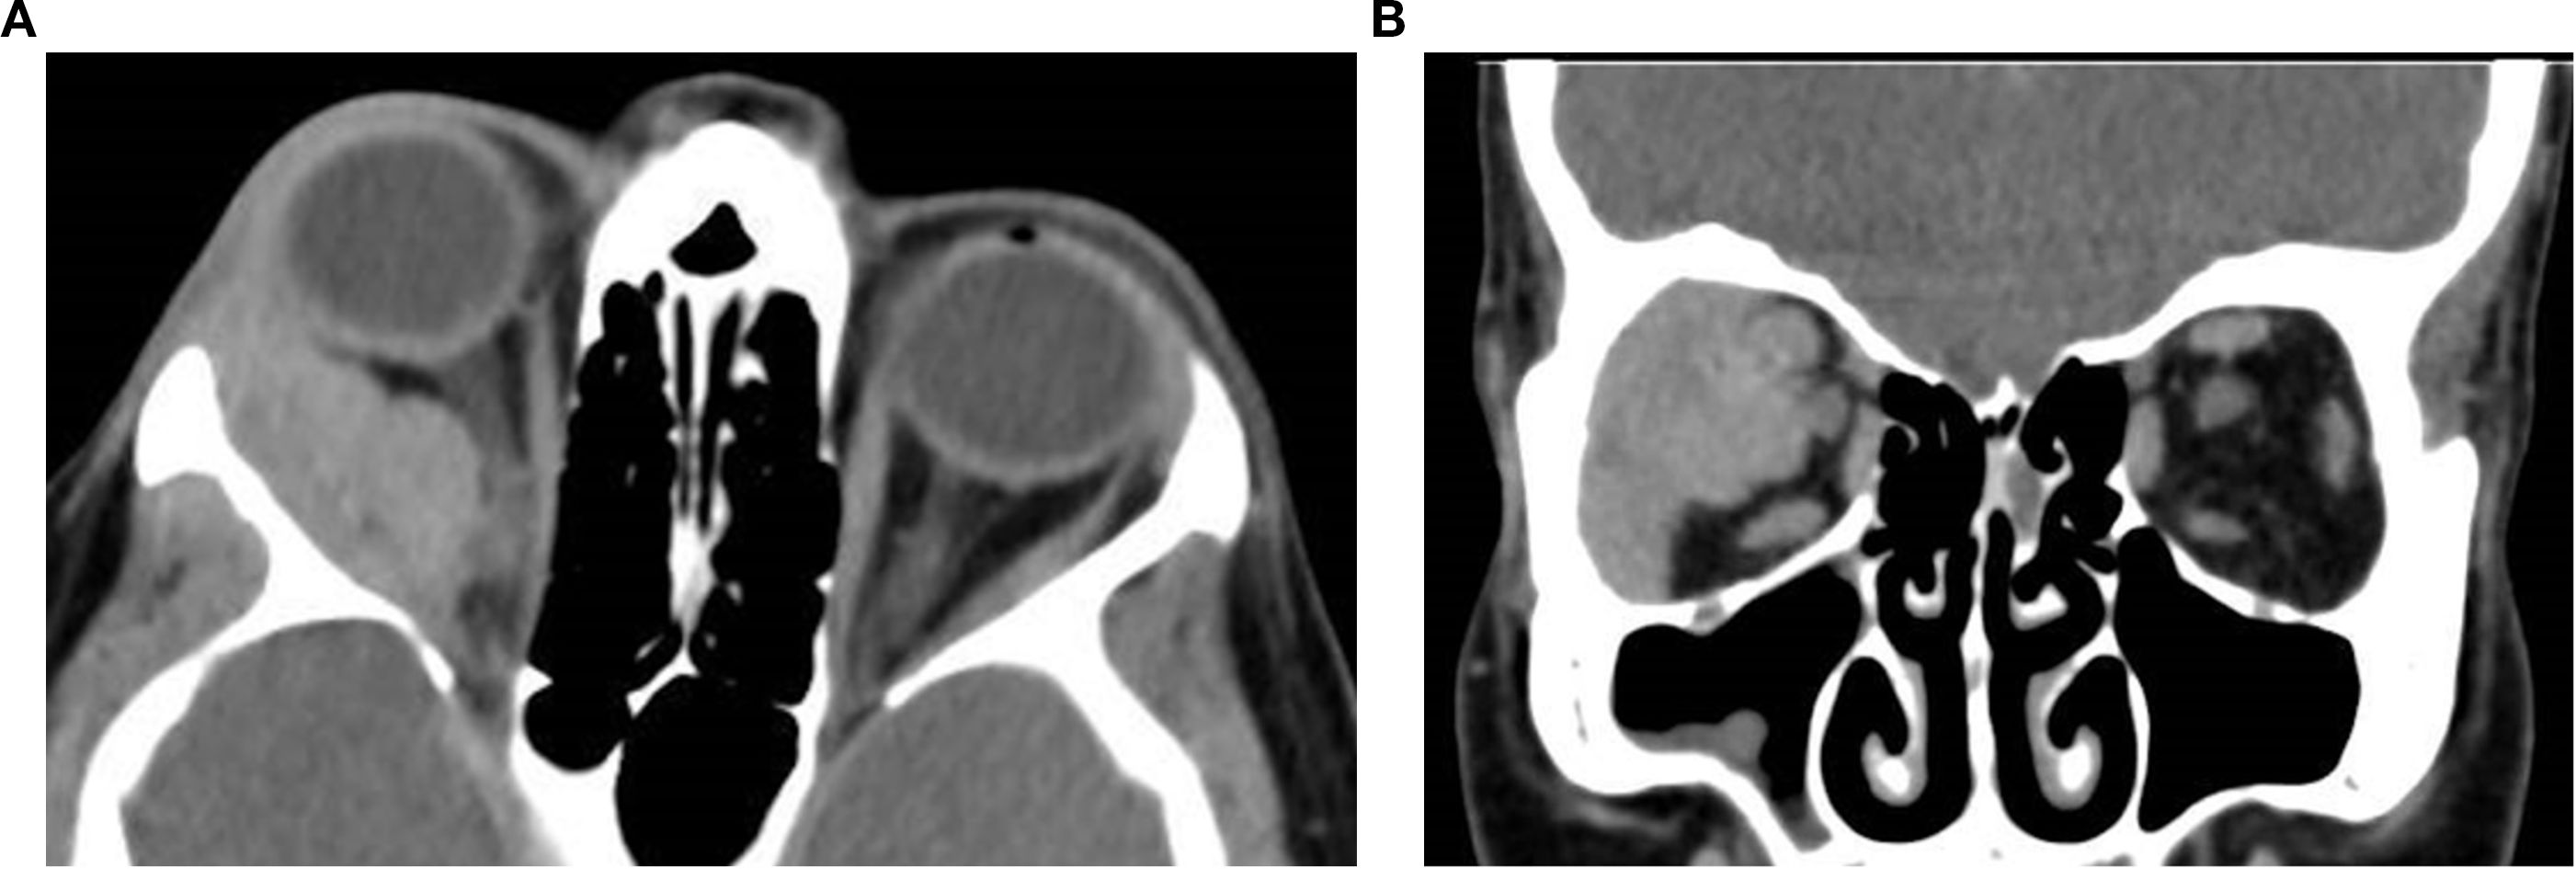

Orbital masses include a diverse spectrum of benign, malignant, inflammatory, and vascular lesions in pediatric and adult patients. Accurately diagnosing the type of lesion is critical, as management strategies differ significantly. Advanced imaging is therefore essential, and computed tomography (CT) is central to orbital evaluation. We reviewed the literature to synthesize evidence on CT features across common orbital pathologies and correlated imaging with clinical presentation to emphasize diagnostic relevance. CT characteristics are summarized for vascular lesions (cavernous venous malformation, lymphatic malformation), inflammatory conditions (orbital myositis, dacryoadenitis), benign lesions (dermoid cyst, pleomorphic adenoma), and malignant lesions (lacrimal gland lymphoma, adenoid cystic carcinoma, rhabdomyosarcoma). We present characteristic patterns of location, morphology, enhancement, and bone change, with practical discriminators and common pitfalls to aid differentiation. When used alongside clinical context, CT remains a preferred modality in many clinical settings due to its rapid acquisition, wide availability, and reliable depiction of bone and calcifications. It supports accurate diagnosis and informed management decisions in time-critical settings. This review provides a structured reference for interpreting CT findings across a wide range of orbital disease.